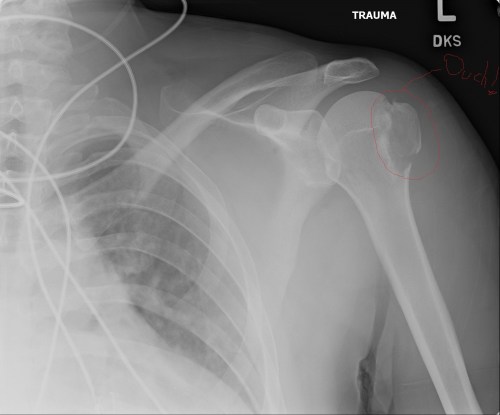

It has been almost three months since my last post here, and things have fallen quiet on our sister blog Anatomy to You, too. I thought it was time for an update, which is mostly a summary of stuff we’ve been doing on my team, but also featuring some interesting images if you stick around. The relative silence here has partly been due to me giving myself some nice holiday time w/family in L.A., then having surgery to fix my right shoulder, then recovering from that and some complications (still underway, but the fact that I am doing this post is itself evidence of recovery).

Stomach-Churning Rating: 4/10; semi-gruesome x-rays of me and hippo bits at the end, but just bones really.

X-ray of my right shoulder from frontal view, unlabelled

Labelled x-ray

Nonetheless, as welfare science likes to term it, it’s entirely “a life worth living”. I have to pick my battles more than I used to, and I’ve had to learn to take more time to get exercise, rest, and avoid the stresses (or even unpleasant people) that can cause my health to take rapid downward spirals. I’m more fragile in many ways, such as having to stop doing karate because my shoulders have weakened. Here’s some interesting anatomy for you from a recent MRI scan of my right shoulder:

My left shoulder in top cross-sectional view, with the missing parts of my humeral head crudely outlined in red. There's more amiss here, too.

My left shoulder in top cross-sectional view, with the missing parts of my humeral head crudely outlined in red. There’s more amiss here, too.

My seizures cause my shoulder flexors to spasm, raising my arms up and crushing my humerus against my glenoid cavity of my scapula and causing occasional dislocations that abrade the humerus against the rim of the glenoid. The result, after numerous seizures, has been the wearing away of the articular cartilage of my shoulder and then the crumbling of the bony head of my humerus. Thus, once my NHS surgeon is ready to in coming months, I am due to have my coracoid process of my scapula cut off and moved, with its attached muscles and ligaments, to be screwed into the front of my glenoid cavity, bracing my humeral head more tightly against the glenoid and thereby resisting future dislocations. Luckily that operation can be done with several small incisions and endoscopy; invasive as the surgery is; thus recovery time won’t be so long.

Latarjet surgery (view of right shoulder joint [glenoid] from front): coracoid process moved posteroventrally. More details (w/videos) here.

It amuses me that all of this intense surgery looming on the horizon doesn’t worry me. I just want it done. I’ve been through a comparable surgery with my left shoulder, involving screwing my greater tuberosity back onto my humerus, so I know what recovery is like, and now that shoulder is doing fine. All that aside, my physical integrity has declined and I feel it every day. I may never return to my karate classes and earn that black belt I was seeking as a life-goal, but time will tell. I am trying to do what I can to remain as strong as I can for as long as I can.